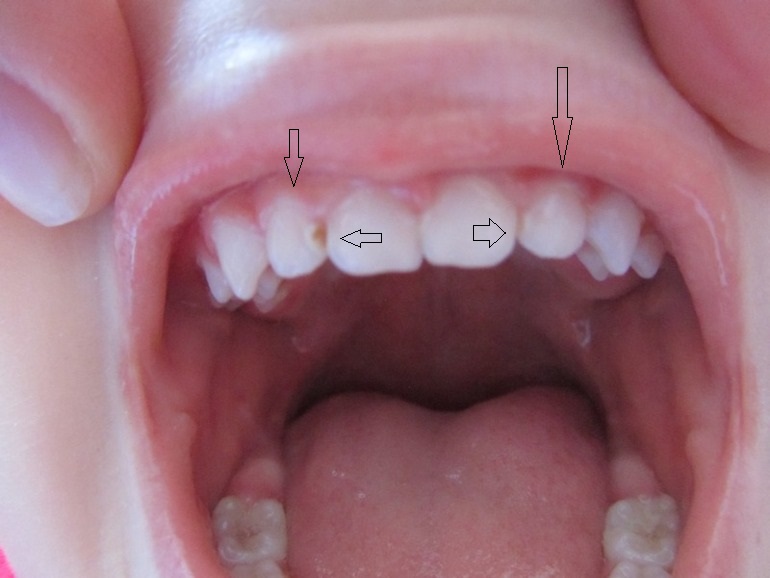

Около месяца назад у сына 2,7 появилась дырочка. Неделю назад ходили в детскую стоматологию, там сказали что передние не сверлят, идите домой и если будет расти то прийти и серебрить. На всякий случай отправили в платный кабинет узнать может фторирование поможет. В платном сказали что фторирование сделают, а между передними зубами нужно пройти бором т.к. они как бы заходят один на другой и там может застревать пища. В другие клиники еще не обращалась. Очень рада что увидела ваши консультации и вчера до полу ночи изучала ваш форум.

Скажите пожалуйста что можно/нужно делать с нашим вторым правым зубом? Серебрение я совсем не хочу применять, может что то другое типа Айкона?

И сегодня когда фотографировала увидела что на втором левом тоже начинает появляться белое пятнышко такое же как на левом. Что делать с ним?

Что значит пройти бором между зубов? это будет такая вертикальная дырка/полоса что-ли после этого?